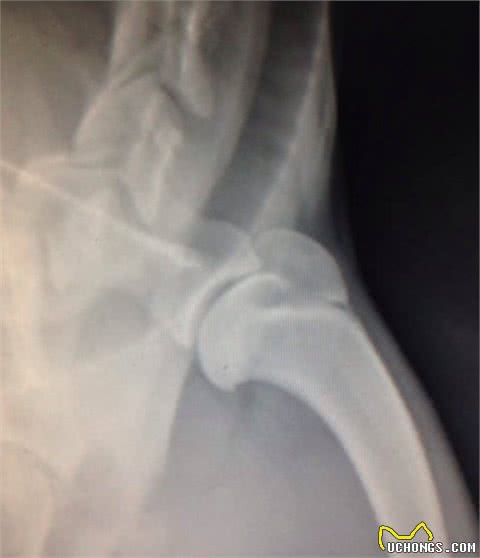

但当这一软骨生长发育异常,患犬被检验出身患分离性骨软骨病,软骨随着而然的非常容易破裂。一般X光片可以观查出小残片。

图为“关节鼠”

11个月小狗肩关节骨软骨病

为了达到准确的评估结果,兽医会请放射科医生为小狗每个患病的部位进行X光片,可清楚了解到疾病的严重程度,而X光片是诊断这类疾病的最常用方式。

一般X光片能够满足诊断需求,但有一种更为精细的仪器叫关节镜检查,可在关节内放置一个小型摄像头,借助它可以直接观察小狗关节腔内的滑膜、软骨、半月板与韧带。

膝关节骨软骨病